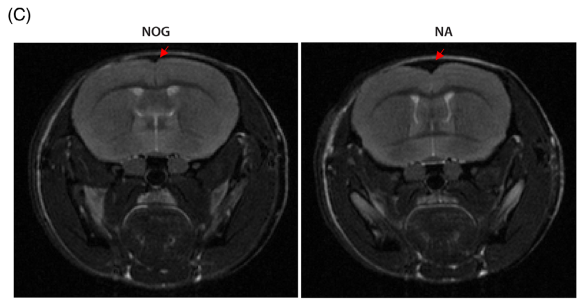

③MRI扫描:12月龄NA小鼠皮质体积减少,脑室扩张。

MRI扫描